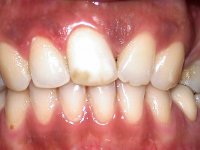

A paciente apresenta um desvio da linha média superior de 6 mm para a esquerda. Resultado da ausência do incisivo central superior esquerdo, os dentes adjacentes inclinaram mesialmente para esta zona, limitando o espaço disponível para a reabilitação prostodontica. Existe uma significativa desarmonia dentária negativa no arco maxilar como resultado da ausência do 21, ausência do primeiro pre-molar com um espaço residual, significativa redução coronária do segundo pre-molar direito, migração dos dentes posteriores para os espaços não preenchidos e uma mesialização molar superior esquerda e direita com uma relação molar em Classe II. Ambos os caninos esquerdo e direito mostram uma relação Classe II na posição de inter-cuspidação máxima. A paciente apresenta uma linha de sorriso média, um biótipo gengival médio grosso, apresenta uma correcta higiene oral sem doença periodontal. Não apresenta hábitos para –funcionais. O exame radiográfico mostra uma significativa inclinação dos eixos dos dentes 11 e 22 com espaço entre a porção apical das raízes. A análise cefalométrica foi feita com o intuito de explorar a hipótese de conseguir arranjar espaço para a colocação de um implante e de uma coroa no local do dente 21. Finalmente a morfologia do osso residual presente na região anterior da maxila foi avaliado com uma TAC, revelando uma perda das dimensões da parede óssea vestibular.

A confecção de um coto de óxido de zircónio com uma coroa de cerâmica vítrea prensada de dissilicato de lítio mimetizou perfeitamente os dentes vizinhos.